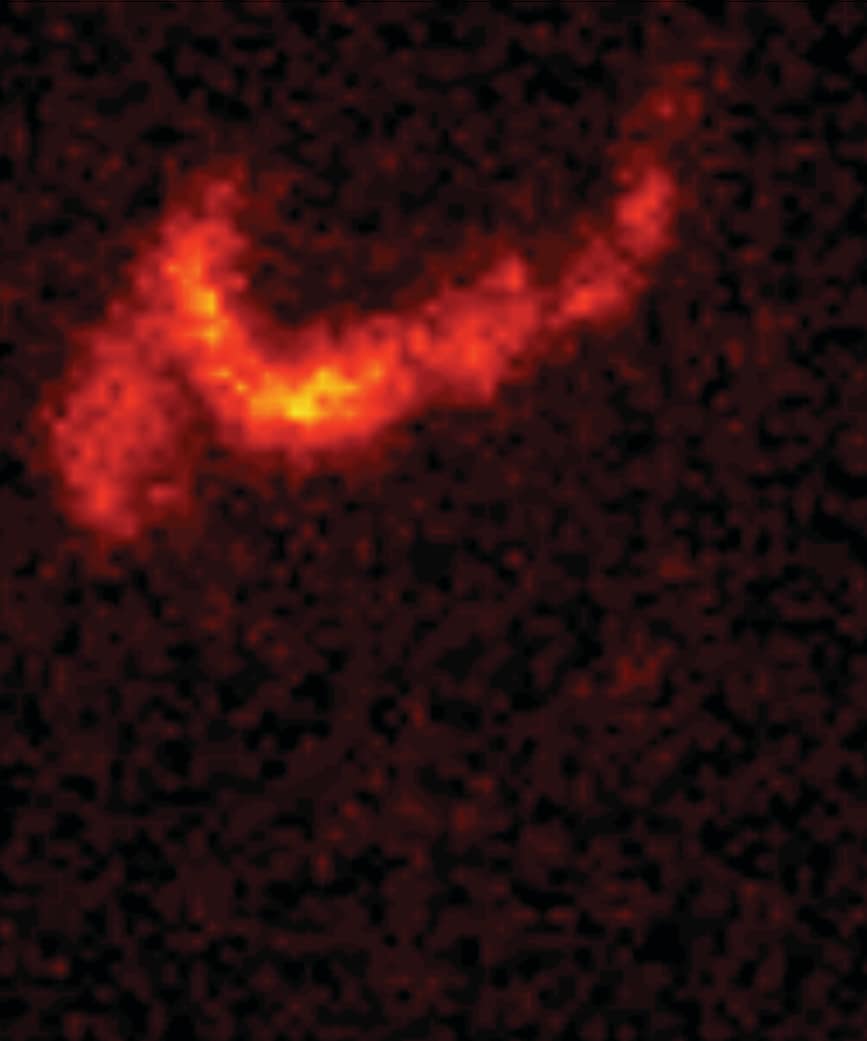

洗腸前

シンチグラフィーの画像について

脊髄損傷患者さんと神経因性大腸機能障害を有する患者さんに対して実施されたシンチグラフィーを用いた研究において、経肛門的洗腸療法は、腸管内容物を排出するのに有効であることが示されました。1

1. Christensen P, Olsen N, Krogh K, Bacher T, Laurberg S. Scintigraphic assessment of retrograde colonic washout in fecal incontinence and constipation. Dis Colon Rectum 2003;46:68–76.